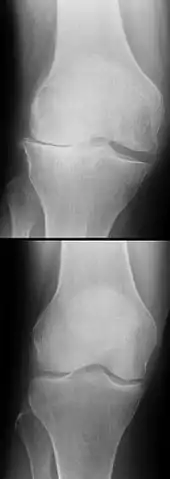

Les ruptures de LC apparaissent la plupart du temps sans cause extérieure, mais par un changement soudain de direction pendant la course ou le saut. Ce sont les blessures les plus courantes cliniquement concernant l'articulation du genou. La rupture des LC peut être diagnostiquée par une étude des symptômes (tiroir antérieur ou extérieur) lors d'un examen clinique et par la description des conditions de survenue de la déchirure. Ce diagnostic peut être confirmé par IRM et arthroscopie. Les ruptures de LC non soignées peuvent conduire à d'importants dommages dégénératifs du genou. Le traitement peut être d'ordre conservatoire ou chirurgical (microchirurgical par arthroscopie). Le choix du traitement, sa date et la méthode à utiliser, font encore l'objet de discussions très controversées. Il est par contre reconnu généralement qu'aucun traitement ne peut actuellement rétablir l'état d'un LC sain. Les suites à long terme d'une rupture de LC comprennent un risque augmenté de formation d'arthrose du genou, indépendamment du traitement effectué.

L'évolution à long terme du genou être commence à bien connue dans le cas des ligamentoplasties, faisant apparaitre un haut niveau de satisfaction subjective à plus de 20 ans chez la majorité des patients, une stabilité antéro-postérieure et rotatoire normale dans 90% des cas, mais aussi une augmentation de signes d'arthrose (concernant surtout les patients ayant eu des lésions cartilagineuses ou méniscales concomitantes), ainsi qu'une altération durable de la proprioception[130],[131]. En revanche, on ne dispose pas d'études à 10 ans ou plus ni pour les protocoles récents de cicatrisation avec attelle, ni pour les toutes dernières techniques de suture chirurgicale[102].